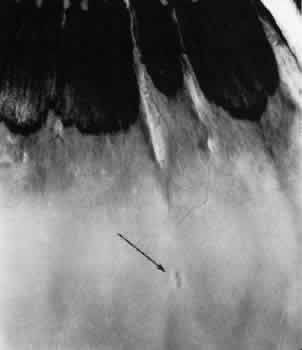

Fig. 12. Enclosed ora bay in a 35-year-old man. Anteriorly, two broad dentate processes converge and join to enclose a bay (island of pars plana). Posteriorly there is a focus of retinal thinning (peripheral retinal excavation; arrow). (× 12.)

PERIPHERAL RETINAL EXCAVATION

Peripheral retinal excavation appears as a rather small oval depression in the retina. Usually this lesion is aligned meridionally with a meridional fold or complex and located 1 to 7.2 mm posterior to the ora serrata (Fig. 13; see Figs. 6 and 12). The focal depression may be surrounded by margins that appear to be elevated; however, microscopic examination reveals that the depression corresponds to afocal loss of the inner retinal layers and that the surrounding tissue is normal (Fig. 14).

Fig. 13. Meridional complexes with peripheral retinal excavation. Two complexes can be seen anteriorly; both contain meridional folds (the fold of complex on the right is discontinuous). Peripheral retinal excavation (arrow) is aligned with the complex on the left (× 12.)